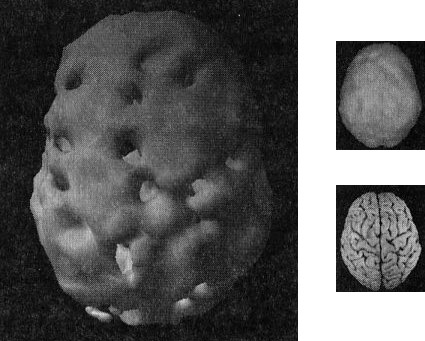

Двадцатилетний Брюс, несмотря на молодость, годами злоупотреблял наркотиками: героином, марихуаной, амфетаминами, галлюциногенами, экстази и обезболивающими. Я познакомился с ним, когда снимал образовательный фильм о вреде наркотиков.

Брюс не был способен завязать со своим пристрастием. Отношения с родными разладились. Он стыдился себя и своего поведения. Как вы сами можете увидеть, мозг 82-летней Анны на томограмме выглядит значительно здоровее поврежденного наркотиками мозга молодого Брюса (рис. 2.7).

Поврежденный наркотиками мозг Брюса

Рис. 2.7 Вид сверху

Значительные повреждения

В норме с возрастом мозг становится все менее активным, поэтому если очень пожилая женщина обладает значительно более здоровым мозгом, чем 20-летний парень, значит, у этого парня серьезные неприятности.